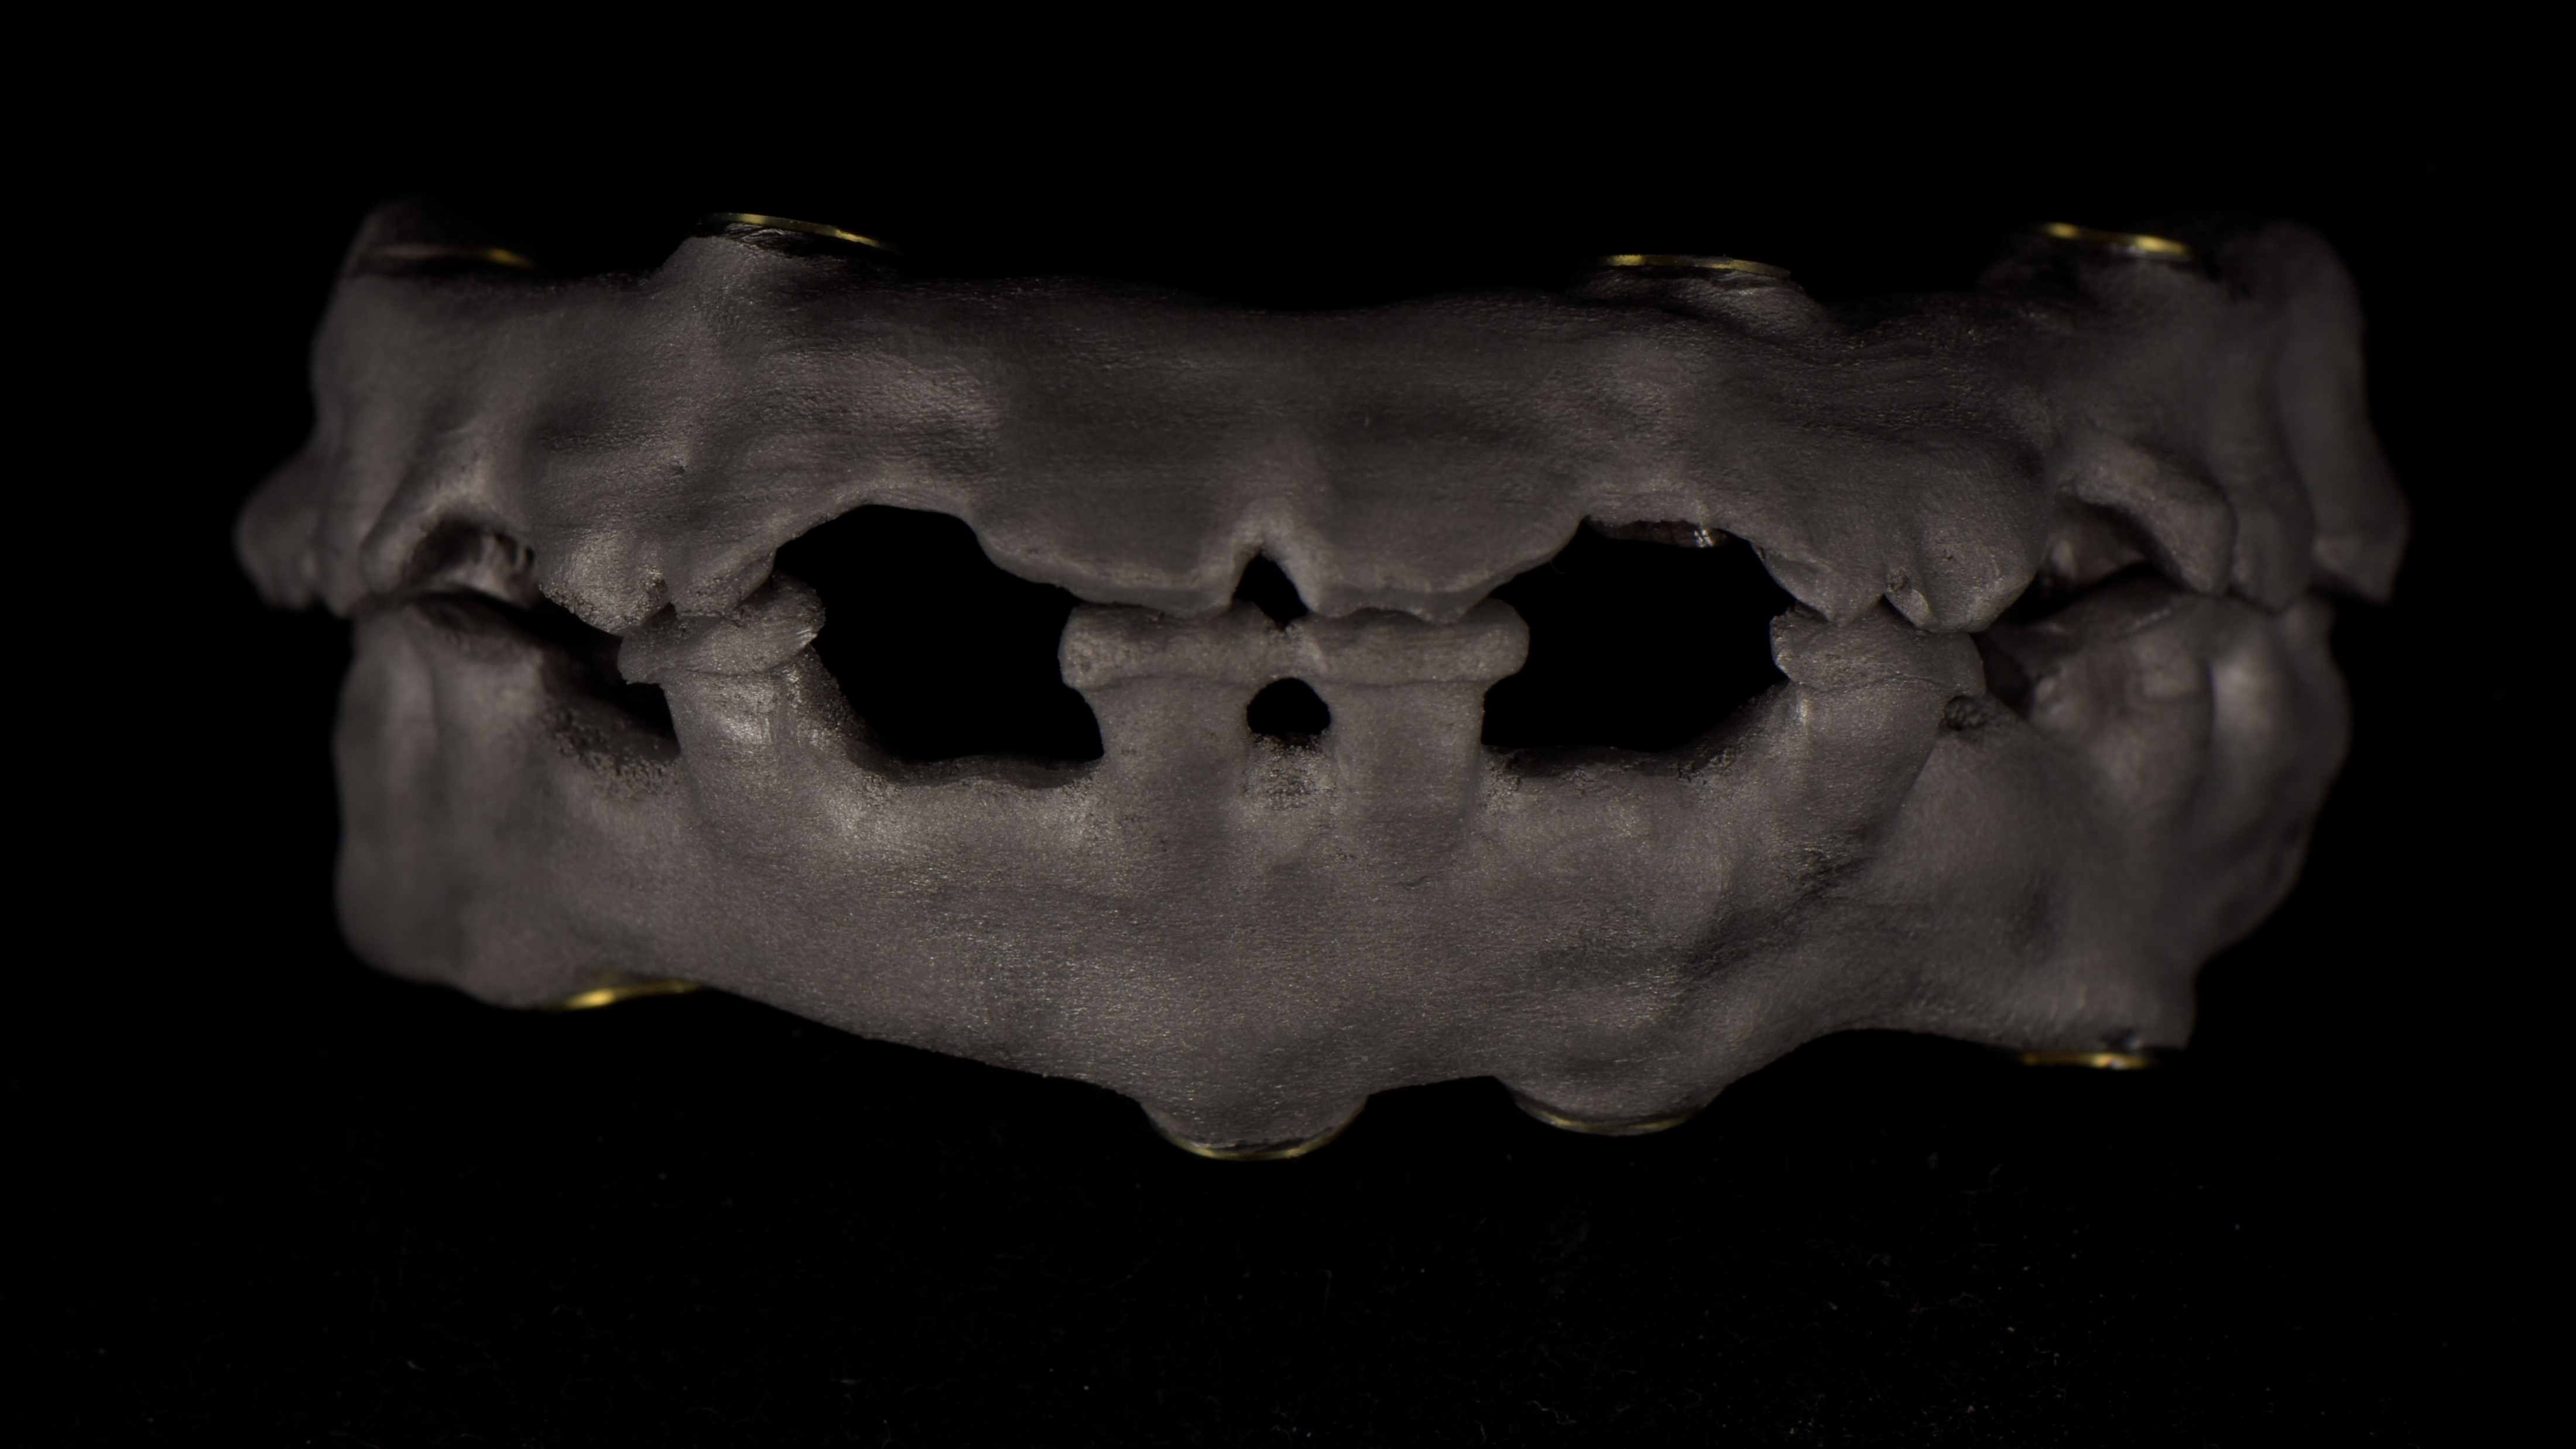

Nell’ultimo incontro prima della finalizzazione delle protesi si verifica la passività ed il corretto accoppiamento protesico di barre in CrCo laser melting sulla base delle quali successivamente sono realizzate le barre in fibra di vetro continuo stampata in 3D. (fig.16-21)

foto 22 produzione barra in fibra di vetro continuo stampata in 3d

foto 23a consolidamento rinforzo in fibra di vetro continuo stampata in 3d a link implantari

foto 23b fasi di lavorazione e stratifica materiale